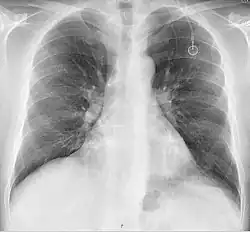

Chest X-ray showing an implanted port

A port is more correctly known as a "totally implantable venous access device". They are also commonly referred to as a Portacath or Chemo port. Brand names include Eco Port, Clip-a-Port, SmartPort, Microport, Bardport, PowerPort, Passport, Port-a-Cath, Infuse-a-Port, Medi-Port, and Bioflo.